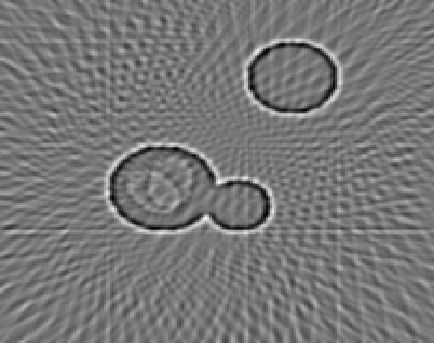

4.1 Reconstruction of the Laplacian feature map

We first investigate the feasibility of the proposed approach for recovering the Laplacian of the initial image. For our first experiment, we use a phantom image, which is defined as a characteristic function of the union of three discs and has the size N×N𝑁𝑁N\times N with N=200𝑁200N=200, cf. Figure 1(a). Since, according to the sampling condition (2.5), full aliasing free angular sampling requires πNs=472𝜋subscript𝑁𝑠472\lceil\pi N_{s}\rceil=472 samples in the s𝑠s-variable, we computed tomographic data at 2Ns+1=3012subscript𝑁𝑠13012N_{s}+1=301 equally spaced signed distances s[1.5,1.5]subscript𝑠1.51.5s_{\ell}\in[-1.5,1.5] and at Nφ=40subscript𝑁𝜑40N_{\varphi}=40 equally spaced directions in [0,π)0𝜋[0,\pi). This data is properly sampled in the s𝑠s-variable, but undersampled in the angular variable φ𝜑\varphi, cf. Figure 1(b).

From this data, we computed the approximate Laplacian reconstruction, shown in Figure 1(c), using the standard FBP algorithm in combination with the LoG-filtered data uLoGsyΘsubscript𝑠subscript𝑢LoGsubscript𝑦Θu_{\rm LoG}\circledast_{s}y_{\Theta} that we computed in a preprocessing step using the LoG data filter from Proposition 3.4. It can be clearly observed that FBP introduces prominent undersampling artefacts (streaks), so that many edges in the calculated feature map are not related to the actual image features. This shows, that the edge maps computed by FBP (from undersampled data) can include unreliable information and even falsify the true edge information (since artefacts and actual edges superimpose). In a more realistic setup, this could be even worse, since artefacts may not be that clearly distinguishable from actual edges.

Figure 4.1: Reconstruction of the Laplacian feature map using FBP. The phantom image of size 200×200200200200\times 200 consisting of a union of three discs (1(a)) and the corresponding angularly undersampled CT data, measured at 40 equispaced angles in [0,π)0𝜋[0,\pi) and properly sampled in the s𝑠s-variable with 301301301 equispaced samples s[1.5,1.5]subscript𝑠1.51.5s_{\ell}\in[-1.5,1.5] (1(b)). Subfigure (1(c)) shows the Laplacian of Gaussian (LoG) reconstruction using the standard FBP algorithm. It can be clearly observed that FBP introduces prominent streaking artefacts that are due to the angular undersampling.